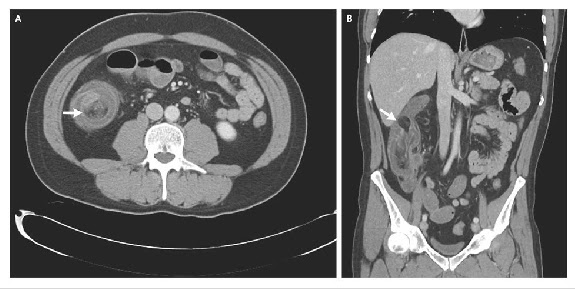

differentiate from gout image :